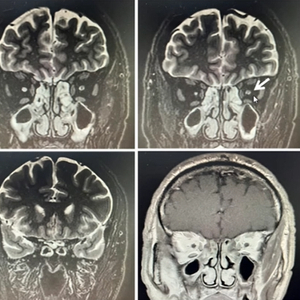

• 视神经MRI:右侧视神经眶内段至颅内段变细、信号增高。左侧视神经眶内段变细、信号增高,无强化。

• 颅脑MRI:左侧基底节区腔隙灶不除外,双侧上颌窦黏膜增厚。